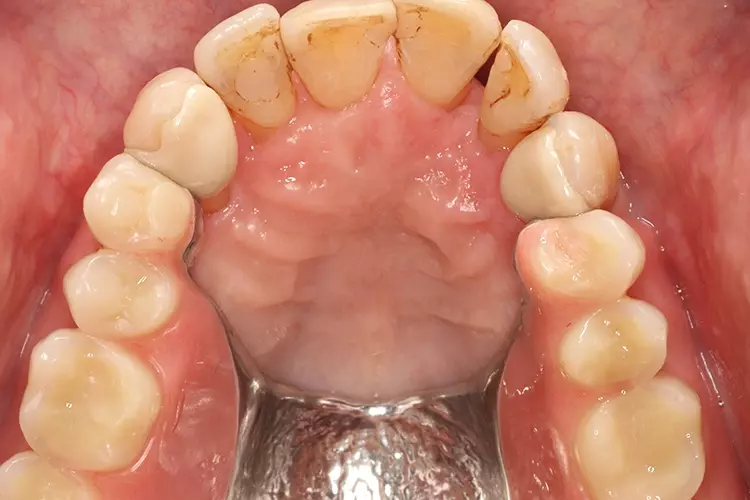

Eine Kippmeiderfunktion und erhöhte Rigidität des Flügels wird durch Gestaltung der zum Prothesensattel weisenden Approximalfläche des Attachments als parallele Anschlagplatte erreicht. Bei ausreichenden Platzverhältnissen lässt sich die Stabilität des Geschiebes zusätzlich erhöhen, indem eine orale Umlauffräsung angelegt wird (Abb. 5 und 6).

Die Präparation erfolgt minimalinvasiv rein schmelzbegrenzt. Zunächst wird die Klebefläche der Pfeilerzähne mit wasserfester Farbe angefärbt sowie die statischen und dynamischen Kontakte mittels andersfarbiger Okklusionsfolie markiert (Abb. 10).

Die definitive Präparation beinhaltet eine leichte zervikale Hohlkehle und zwei approximale leicht konische Retentionsrillen. Bei Frontzähnen werden noch eine inzisale Abschlusskante, eine Noppe sowie eine leichte palatinale Veneerpräparation angelegt (Abb. 11 und 12). Bei Seitenzähnen ist eine zusätzliche okklusale Auflage zu präparieren (Abb. 13).